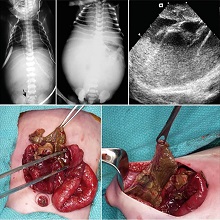

Анеуризма аорте је локализовано, трајно проширење крвног суда од најмање 50% ширег пречника, у односу на крвни суд здраве особе истог пола и старости, а која садржи сва три слоја зида. |

| Акутни холециститис је акутно запаљење зида жучне кесице праћено болом у трбуху под десним ребарним луком. Чести симптоми су још и повишена телесна температура, мучнина и повраћање. У око 90% случајева удружено је са билијарном калкулозом (камен у жучној кесици). Акутни холециститис се најчешће јавља као акутна егзацербација хроничног холециститиса. |